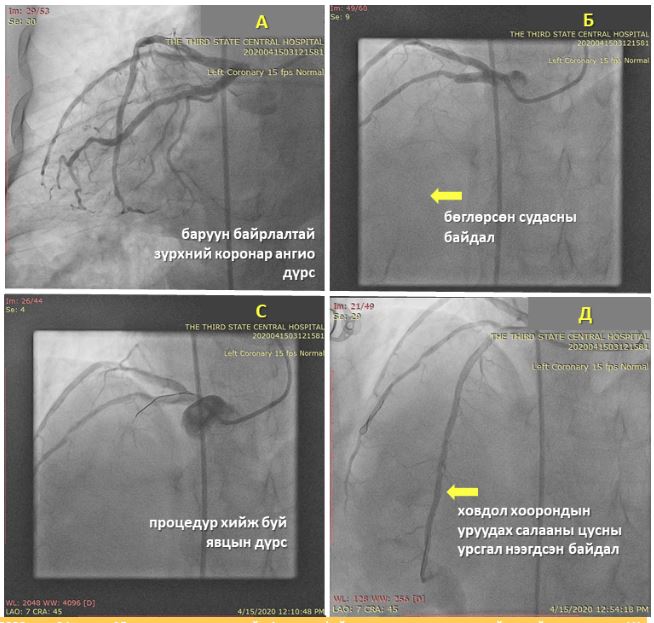

Тус эмнэлгийн Ангиографийн оношилгоо, эмчилгээний тасгийн зөвлөх эмч, Анагаах ухааны доктор, профессор З.Лхагвасүрэн ахлагчтай судсан дотуурх мэс засал эмчилгээний баг энэ сарын 15-нд төрөлхийн баруун байрлалтай зүрхтэй 57 настай эмэгтэйд титэм судсан дотуурх мэс заслын аргаар баруун цавины артериар дамжиж баруун байрлалтай зүүн титмийн артерийг сэтгүүрдэж, архаг бөглөрөлт бүхий ховдол хоорондын уруудах салааны судсанд хоёр ширхэг эмтэй тэлэгч стентийг суулгаж, титмийн цусны урсгалыг нээж, зүрхний булчингийн цусан хангамжийг сэргээх эмчилгээг амжилттай хийн, амь насыг нь аварлаа.

Төрөлхийн баруун байрлалтай зүрх нь төрөлхийн ховор байрлалын нэг бөгөөд ойролцоогоор 10 мянган хүн амд нэг тохиолддог гэж үздэг. Хэвийн бус байрлалтай зүрх хэдий ч титэм судасны эмгэгүүдийн тохиолдох хувь нь ердийн байрлалтай хүн амаас ялгарах зүйлгүй байдаг байна.

Баруун байрлалтай зүрхтэй хүний титэм судасны эхлэл хэсгүүд хэвийн бус байрлалтай байдаг онцлогоос шалтгаалан титэм судсан дотуурх мэс заслын аргаар оношилгоо, эмчилгээ хийхэд стандарт арга барилаас өөр байдаг тул зарим тохиолдолд өвөрмөц, тусгай зориулалтын хэрэгсэл ашиглах шаардлага гарч, ажилбар хийж буй эмчээс илүү туршлага, ур чадвар шаарддаг юм.